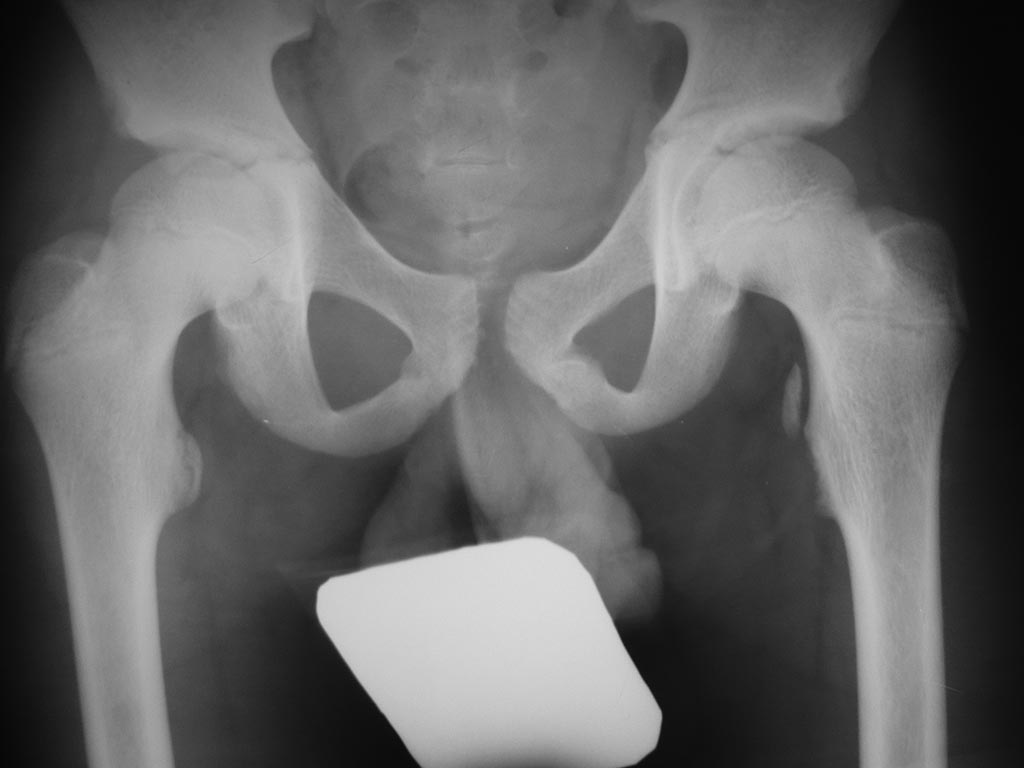

Пациент 12 лет Травма при неловкой постановке ноги во время бега Давность травмы 2 суток Диагноз: З/эпифизеолиз малого вертела левого бедра со смещением

Диагноз : Апофизеолиз малого вертела левой бедренной кости со смещением.